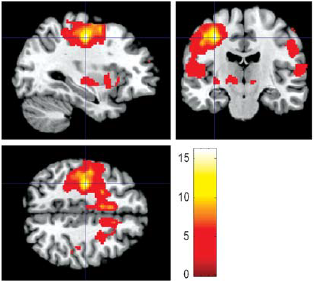

This webpage is about people in Malaysia who study human brain function using functional magnetic resonance imaging (fMRI) technique and their research. The data obtained from their study are analyzed using statistical parametric mapping (SPM) and dynamic causal modeling (DCM).